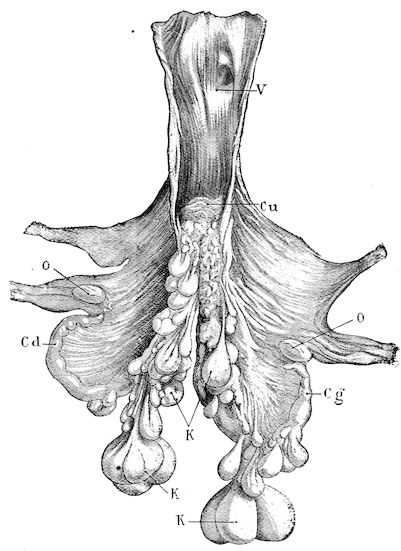

Fig. 3.—Pig suffering from osseous cachexia (fourth stage).

114. The fourth phase, or period of osteomalacia, i.e. softening of the bones, is also the last. It is rarely seen in large animals like horses and oxen, because accidents so often accompany the preceding stages and necessitate slaughter; but it is common in goats and pigs.

In this phase the bones become elastic, soft and depressible, yielding to the pressure of the operator’s fingers.

Fig. 4.—Deformity of the face in the horse shown in Fig. 2.

The flat bones are particularly liable to this change, which is common to domesticated animals. The bones of the head are the first to suffer; later those of the pelvis. The lower jaw becomes swollen, particularly about the centre of the branches which may attain three, four, or five times, their normal thickness.

The depression in the submaxillary space disappears. The upper jaw undergoes similar changes, becoming deformed and thickened until the cavities of the sinuses and the hollow appearance of the palate are lost, while the face is so changed that it cannot be recognised as that of a horse, goat, etc.

The molar teeth are almost buried, their tables alone being visible at the bottom of a depression, the edges of which rise above the neighbouring parts (pig).

Mastication is clearly impossible, the jaws appear paralysed, the muscles powerless, and only swallowing is possible, a fact which explains why life is only prolonged to this stage in animals which can be fed with a spoon or bottle (pigs and goats). The bones of the cranium, although greatly changed in texture, are always less deformed than those of the face.

The changes are such that it is often easy with a mere post-mortem knife to cut the head completely in two. Osseous tissue, properly so-called, has disappeared.

All the constituent tissues, with the exception of the skin and muscles, i.e., the bone, periosteum and aponeuroses, have the appearance and consistence on section of the fibro-lardaceous tissue seen in chronic inflammation.

Fig. 5.—Head of a pig suffering from osseous cachexia.

In the goat, the disease shows some slight peculiarities. Thus, in the second phase, during which goats and sheep suffer so markedly from lameness and pain in the bones, goats often walk on the knees. The disease, however, is uncommon in these animals. The phase of osteoclastia is also less marked and fractures are rare, because the animals weigh less and also because they are less exposed to falls and violent shocks. The bones, nevertheless, are extremely fragile and fractures may be produced at will.

Osteomalacia, on the other hand, is always well marked.

Regarding the development of the disease in pigs, we may repeat what has just been said respecting the goat. Walking on the knees is often one of the first signs, fractures are somewhat rare, and the period of softening and deformity is always very noticeable.

Fig. 7.—Osseous cachexia: softening of the maxillæ.

Fig. 8.—Transverse section through the middle region of the face in a pig suffering from osseous cachexia.

18In the final stages, the bones may be cut with a knife, and a time arrives when bony tissue seems completely to have disappeared; thus, as shown in Fig. 8 herewith, it was possible to cut the entire head of a pig into thin slices without the slightest difficulty. All parts of the head had been affected by the softening change.

From the chemical point of view, the diminution in mineral salts and in phosphate of calcium has long been recognised, but the degree of this change varies according to the phase. In human beings the proportions have been estimated as follows: Normal bone, 50 to 80 per cent. of phosphate of calcium; bone in persons suffering from osteomalacia, 5 to 20 per cent. of phosphate of calcium. The changes in the ossein have not been carefully studied. We only know that histologically the ossein becomes fibrillar, and that chemically it no longer retains its normal composition.